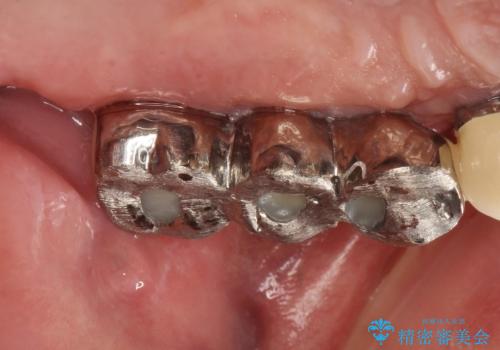

虫歯だらけ、歯周病 崩壊した口腔の再建 フルマウスリコンストラクション

かみ合わせの力が非常に強く、夜間の歯ぎしり・食いしばりもひどかったため、奥歯はメタルオクルーザルの設計でかぶせ物を製作しています。

かぶせ物の種類:PFZ / PFM metal occlusal